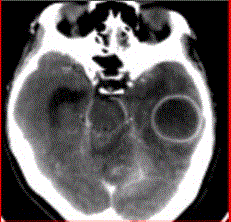

问题 患者女,26岁,头痛、低热10d余,既往有左侧慢性中耳炎病史。CT表现如下图。 MRI检查中,脑脓肿最敏感的方法或序列显示是

选项 A.T2*WI B.DWI C.FLAIR D.T2WI E.PDW

答案 B